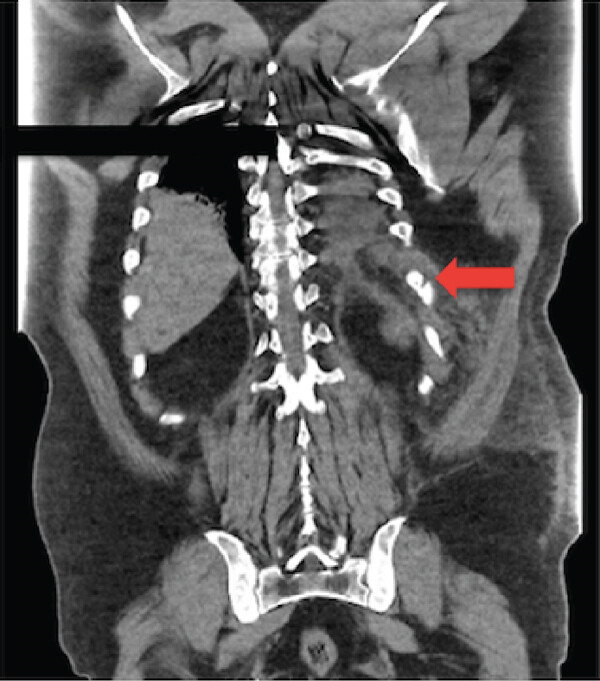

Спустя два дня он вновь обратился в клинику по причине выраженной боли в груди. При физикальном обследовании была выявлена ​дыхательная недостаточность легкой степени, умеренная гипертензия, тахикардия и тахипноэ (ЧДД 22 вдоха/мин) с сатурацией кислорода 95% на воздухе, экхимозы и болезненность в левой нижней части грудной клетки, а также двусторонние хрипы, наиболее выраженные в нижнем отделе левого легочного поля. Лабораторные исследования показали лейкоцитоз со сдвигом влево (18 000/ мкл), умеренную гипонатриемию (134 ммоль/л), гиперхлоремию (117 ммоль/л) и повышение СОЭ (30 мм/ч). Тест на SARS-CoV-2 был отрицательным. Рентгенография грудной клетки выявила узловые затемнения в левой нижней доле легкого без выпота. КТ грудной клетки (рис. 1) показала минимально смещенный перелом X ребра и небольшое скопление жидкости и ателектаз слева.

Рисунок 1. КТ-снимок грудной клетки в коронарной проекции (при поступлении) показывает минимально смещенный поперечный перелом X ребра (красная стрелка).